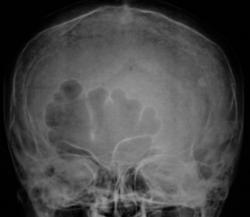

Представлены, на диске, такие изображения черепа.

Представлены, на диске, такие изображения черепа. Что посоветуете уважаемые коллеги?

Структура затылочной кости не совсем обычная...похоже на "пробойниковые отверствия"...касаемо лобных пазух - такой "фасон", мне кажется это природа, и мало вероятно, что ендокринология...

Кости свода толстоваты, пазухи крупные. Турецкое седло не изменено. По-моему, стоит беспокоиться, только если есть эндокринные нарушения.

Файзуллин, если мне не изменяет память, частенько, гиперпневматизацию пазух связывал с опухолевым ростом. Но в данном случае, по всей видимости, вариант или аномалия развития лобной пазухи.